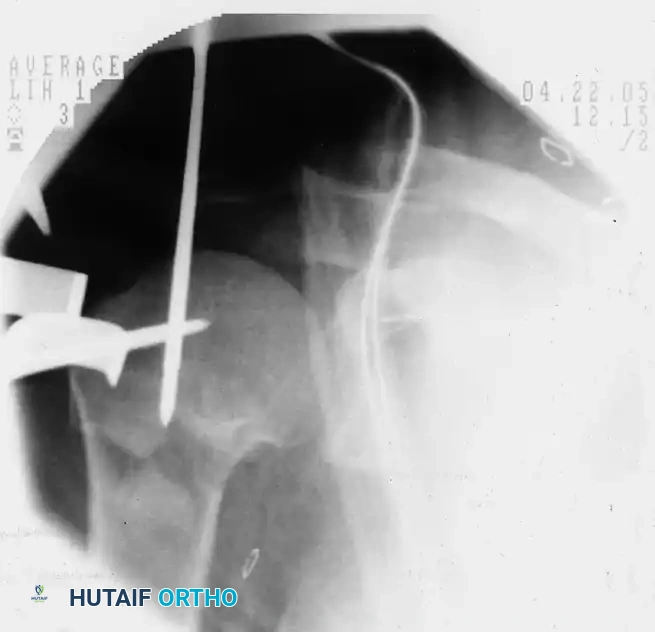

Preoperative fluoroscopic evaluation demonstrating a two-part surgical neck fracture of the proximal humerus, an ideal candidate for the anterolateral approach.

A threaded pin is inserted into the humeral head fragment, serving as a "joystick" to manipulate and reduce the fracture prior to definitive fixation.

Placement of the initial guidewire into the proximal humerus, ensuring the correct entry trajectory for antegrade nailing.

Fluoroscopic confirmation after nail insertion and the placement of multi-planar proximal locking screws.